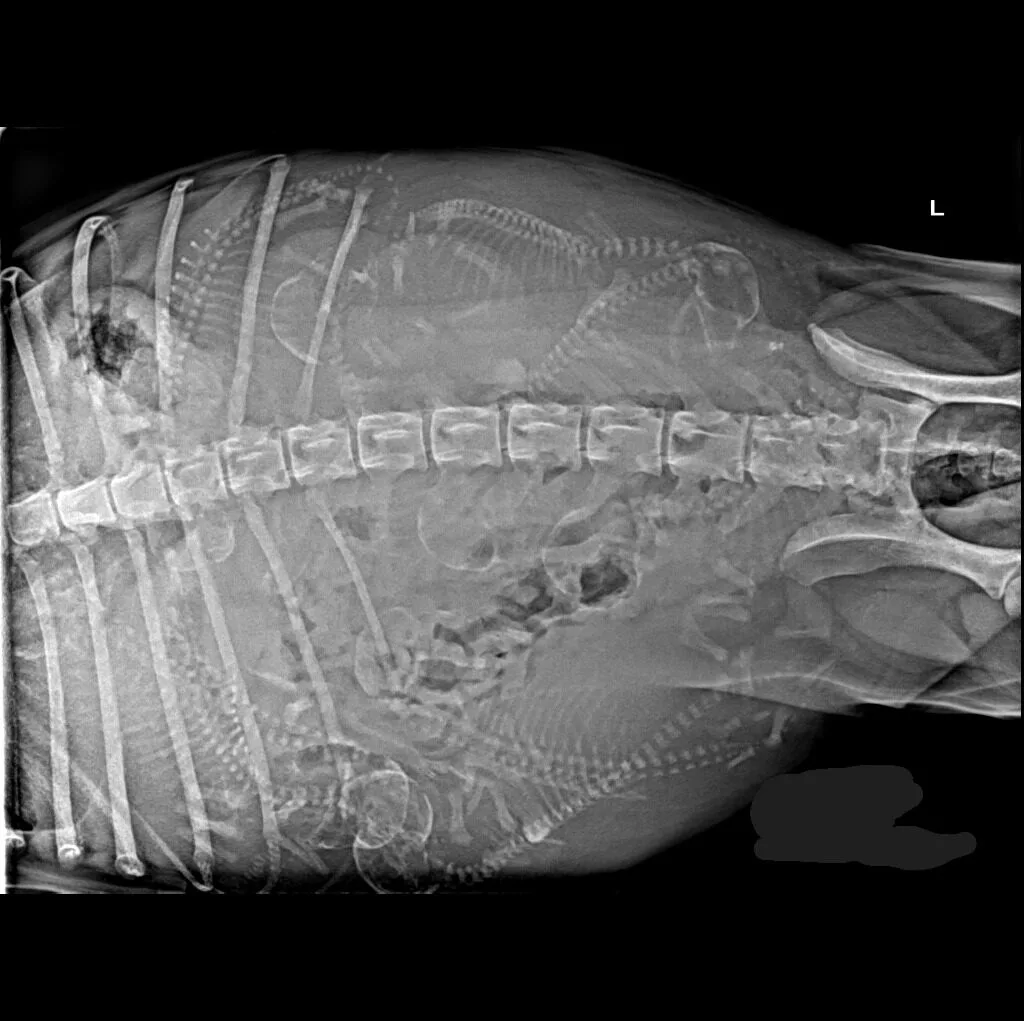

🔹 Abdominal & Gastrointestinal Issues – Detecting obstructions, tumors, or organ abnormalities

🔹 Cardiac & Respiratory Conditions – Evaluating heart disease and lung disorders

Digital radiography offers superior imaging quality and precision compared to traditional X-ray techniques. It allows us to detect hidden health issues early, leading to faster and more effective treatments.